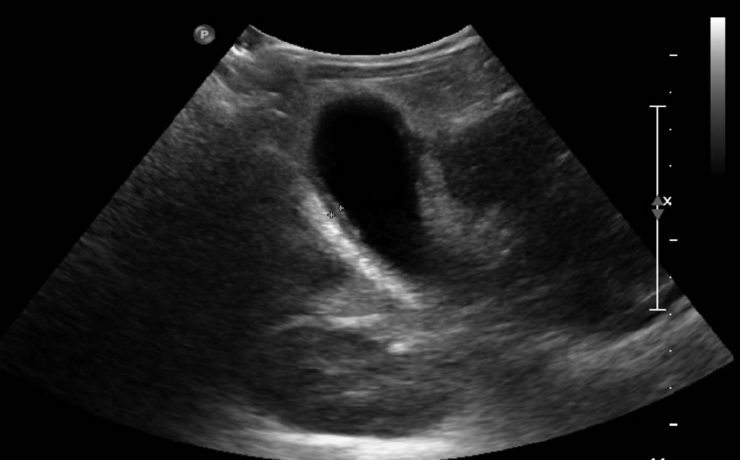

Las lesiones solidas clásicamente podemos diferenciarlas en alta, intermedia y baja celularidad. Las de alta celularidad son aquellos que poseen una gran cantidad de células, vasos edema y un rápido potencial de crecimiento e invasión. Suelen ser en la etapa inicial redondeados de bordes netos, marcadamente hipoecoicos y homogéneos, con